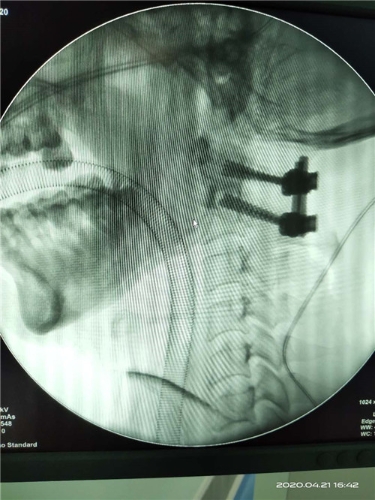

术后透视

微信图片_20200507143111